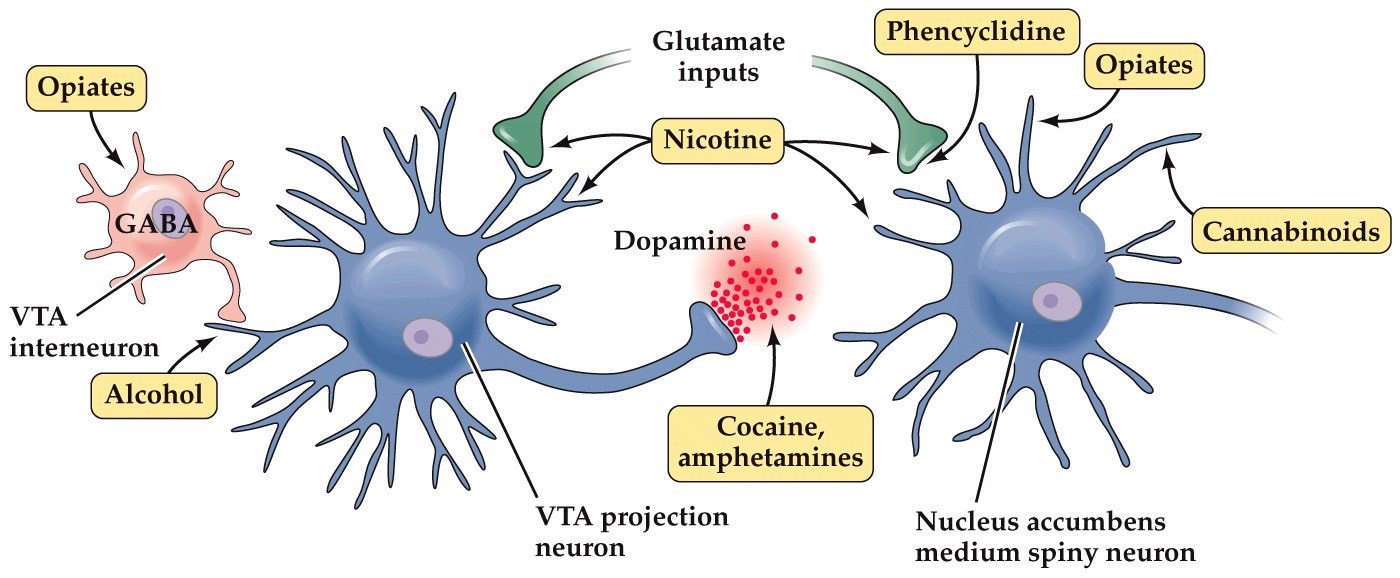

Drug abuse and addiction

- Emotional processing in the limbic system signals the presence or prospect for reward and punishment, and activates programs to procure rewards and avoid punishment

- Most known drugs of abuse (heroin, cocaine, ethanol, opiates, marijuana, nicotine, amphetamines) act on the limbic circuits

- Most act by altering dopamine circuits that go through the ventral basal ganglia

Note:

all act by changing the neuromodulatory influence of dopamine for processing reinforement signals in nucleus accumbens, leading to the strenghthening of circuits underlying addictive behavior in limbic systems

Substances of abuse affect dopamine projections from the VTA to the nucleus accumbens

Note:

Exposure to drugs of abuse causes long-lasting enhancement of excitatory input to VTA dopamine neurons, increasing AMPA/NMDA receptor ratio at these synapses.

Circuits involved in substances, "drugs", of abuse

- Nicotine enhances input onto VTA by presynaptic excitation

- Opioids, benzodiazepines, and cannabinoids act by hyperpolarizing GABAergic neurons

- Ethanol boosts dopamine concentrations– mechanism unknown

- Cocaine blocks dopamine reuptake via the plasma membrane dopamine transporter (DAT)

- Ecstasy causes dopamine release in vesicle independent manner, inhibits

- Dopamine degradation and increases dopamine biosynthesis

Note:

Specifically, studies in primates and rodents have shown that many VTA dopamine neurons encode reward prediction errors. This error signal is hypothesized to direct synaptic plasticity in target neurons in the nucleus accumbens and prefrontal cortex for reinforcement-based learning. If VTA dopamine neurons signal a reward, the action or behavior that immediately preceded the reward is reinforced through dopamine modulation of downstream circuits (see Figure 10–44). Drugs of abuse bypass natural signals that activate these dopamine neurons, thus dissociating the reward system from its natural stimuli. Specifically, by increasing dopamine concentration at dopamine neurons’ presynaptic terminals, drug consumption mimics dopamine neuron activation; this reinforces the preceding actions, include drug consumption itself. Thus, addictive drugs hijack the brain’s reward system and exploit mechanisms that otherwise regulate learning and motivational

Addictive substances hijack the brain’s reward system by enhancing the action of VTA dopamine neurons

- Addiction: compulsive subtance intake despite long-term negative consequences

- All drugs of abuse increase dopamine concentration at the output targets of the ventral tegmental area

- Nucleus accumbens– processes reward information

- Prefrontal cortex– goal selection and decision making

Key components of limbic system reward circuits

- VTA–nucleus accumbens pathway:

- Dopamine pathway

- Acts as a rheostat of reward. Tells other brain centers how rewarding an activity is. The more rewarding an activity is deemed, the more likely the organism is to remember it well and repeat it

- Neurons from ventral tegmental area (VTA) to nucleus accumbens (major neurotransmitter is dopamine)

- Critical pathway for drug addiction